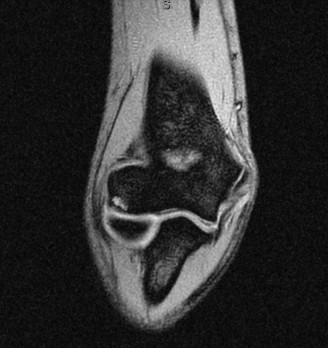

Which of the following findings is indicative of a subscapularis tendon tear?

The answer is (B). As the four layers of the lateral rotator interval insert onto the lesser tuberosity of the humerus, they form the “reflection pulley” that forms a sling around the tendon of the long head of the biceps before it enters the bicipital (intertubercular) groove. A tear of the upper part of the subscapularis can disrupt this reflection pulley and destabilize the biceps tendon, allowing it to sublux or even

dislocate out of its groove, usually in a medial direction. If this happens, the intertubercular groove will be empty on MRI. Often, a “pulley sign” will also be seen on MRI when this occurs. This is when contrast material extravasates extra-articularly just over the superior border of the subscapularis tendon on axial images (see Fig. 2–11).

Figure 2–11_Axial T1 MRI. Left: an empty intertubercular sulcus, positive pulley sign (straight _black arrow on left), and dislocated biceps tendon (curved black arrow). Right: fraying subscapularis tendon (arrow). (From Lyons RP, Green A. Subscapularis tendon tears. J Am Acad Orthop Surg. 2005;13(5):353–363.)